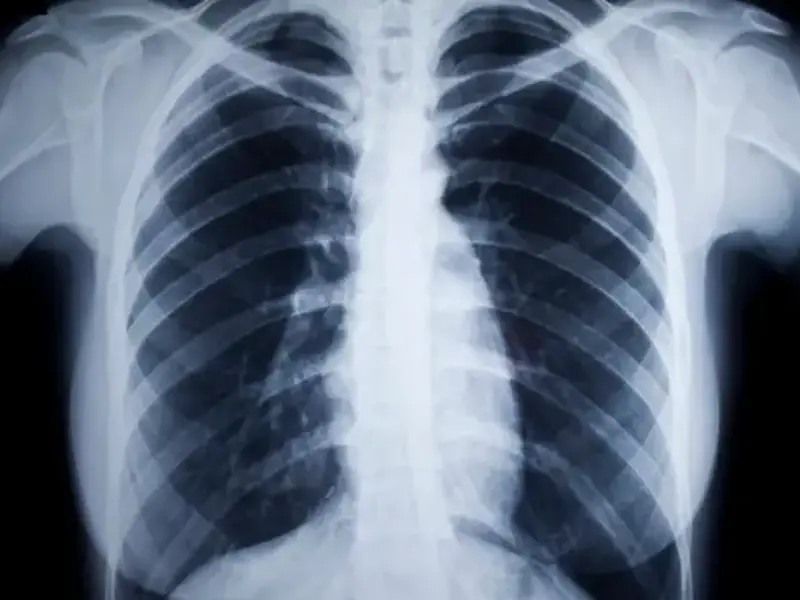

Obstructive sleep apnoea is a prevalent condition associated with significant comorbidities. Discover what you should know about identifying and managing this condition in primary practice with the clinical fact sheet summary. 30mins each of RP and EA CPD are available with completion of the quiz.